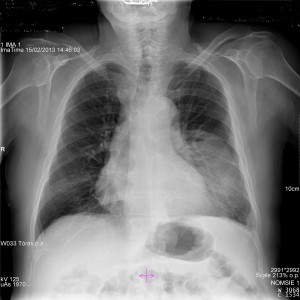

Caso 49

Autor:

Ana Sánchez Espallardo/María Ángeles Saura Nuñez